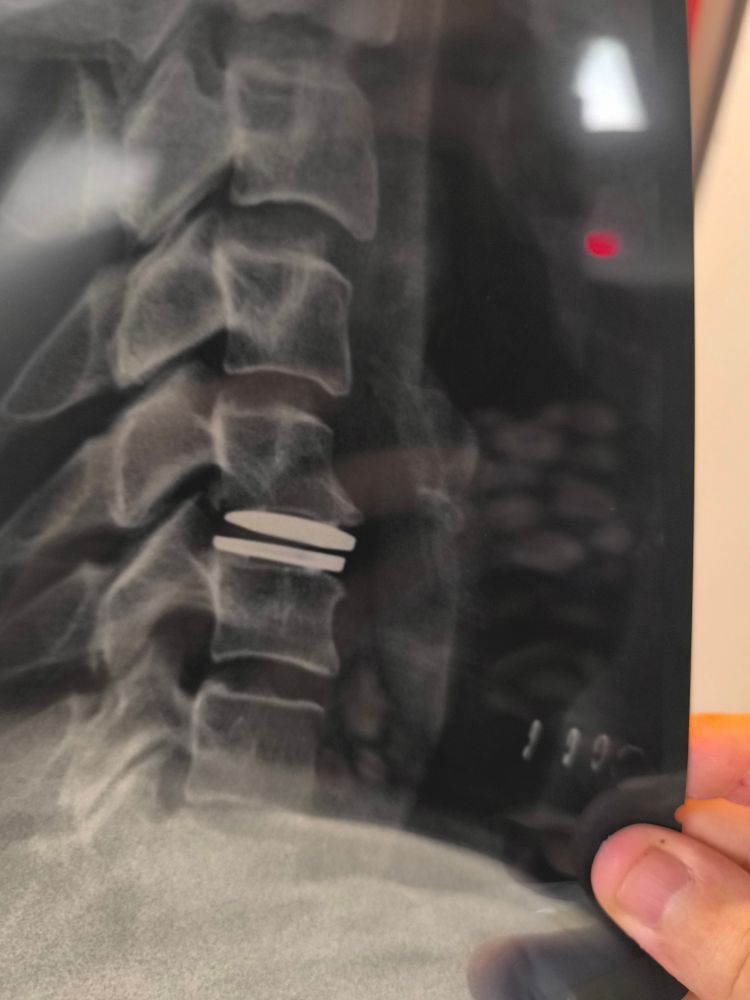

J'adore la présentation de la prothèse sur le site du constructeur mdr

L'homme qui valait trois miyards

Nerf brachial comprimé

Nerf brachial malmené

Mais nerf brachial libéré. Ciao la méchante hernie format Godzilla qui était en train de me priver de mon bras gauche. J'ai sneak in des p'tits pims j'ai mon PC je suis heureux jusqu'à ce qu'on me foute dehors demain.